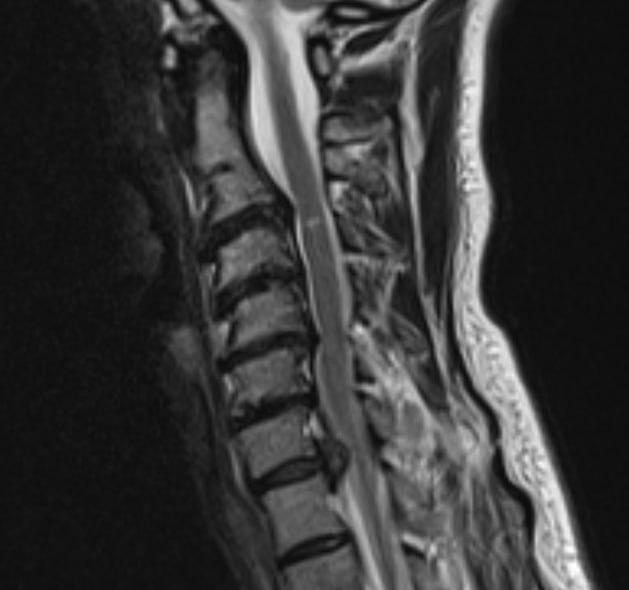

Сильная боль в шее, отдающая в левую руку, заставила обратиться в Долгопрудненскую больницу пациентку 45 лет. Целый месяц женщина испытывала мучения. Обследование на аппарате магнитно-резонансной томографии показало, что болевой синдром вызван крупной грыжей межпозвонкового диска.